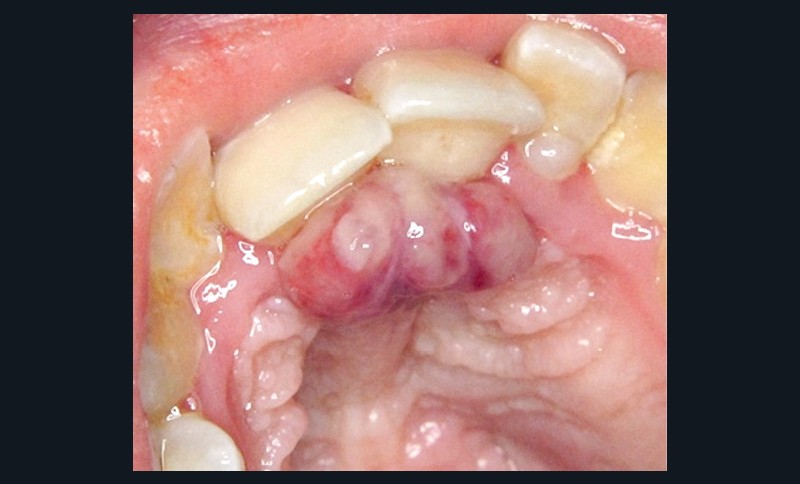

- Forme gravidique fréquente au 2e et 3e trimestres (fig. 1b). Favorisée par l’augmentation du taux de progestérone, œstrogènes, prostaglandines entraînant une vasodilatation.